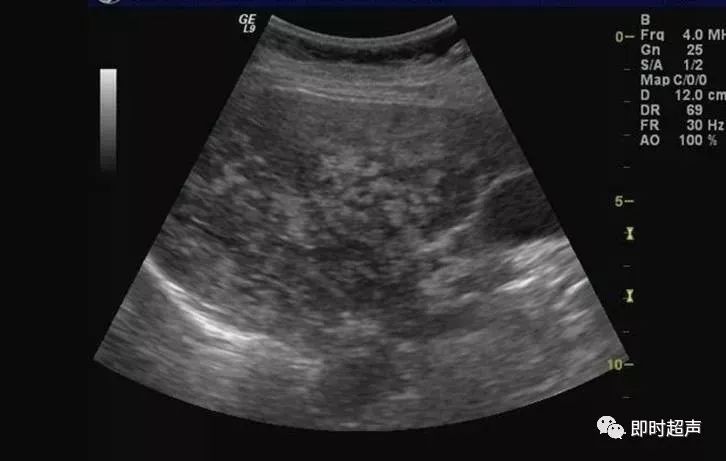

超声表现:

1、肝实质回声细密增强,呈云雾状,后方回声衰减。

2、肝内管道结构显示欠清。

3、肝肾对比阳性,正常情况下肝脏回声略高于肾实质回声,脂肪肝时肝脏回声明显增强。

4、肝脏增大,形态饱满,边缘变钝。

轻度:肝回声增强,后方回声衰减不明显,肝内管道结构显示正常。

中度:肝回声明显增强,后方回声衰减,肝内管道结构显示欠清晰。

重度:后方回声衰减明显,后方肝组织显示不清,膈肌显示不清。